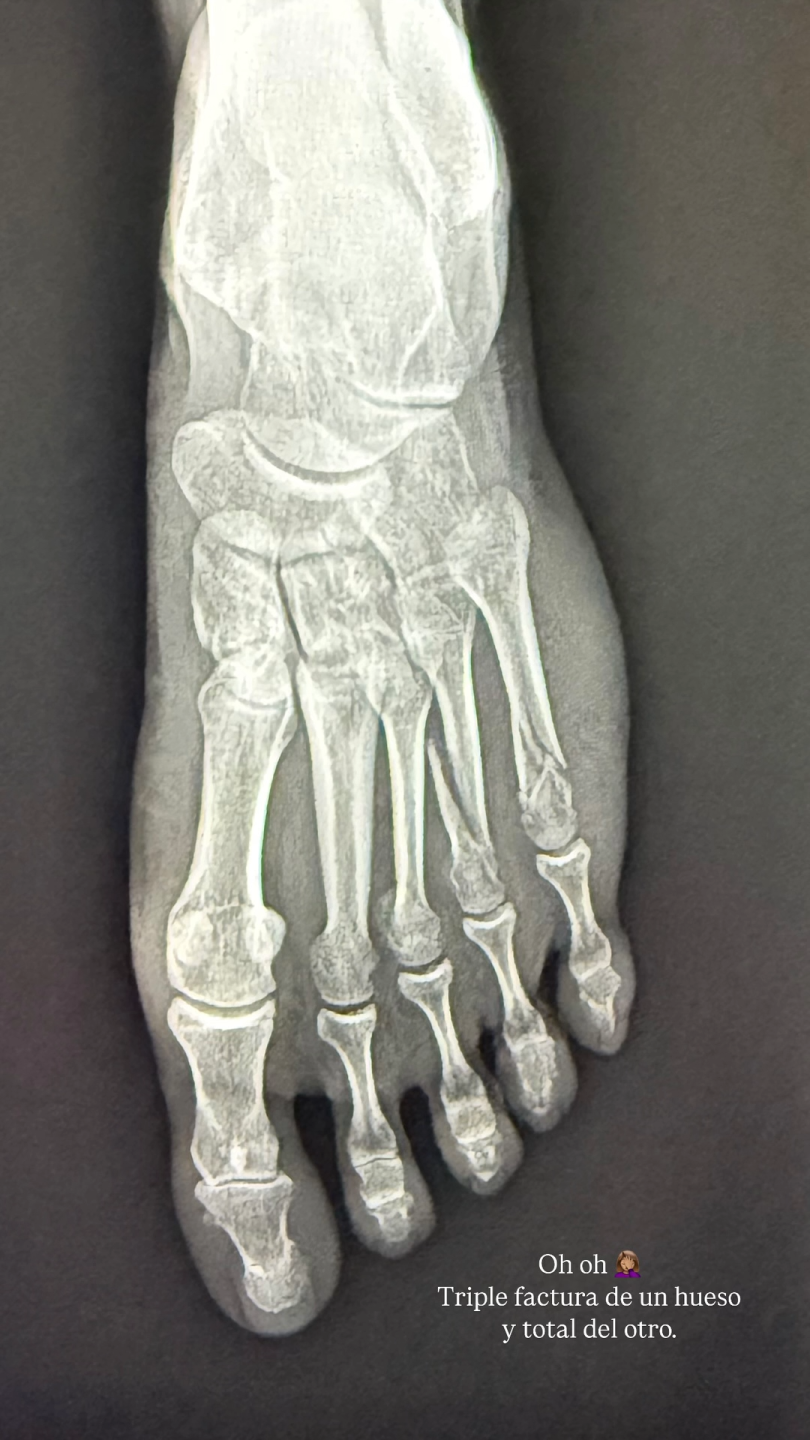

En la siguiente foto ya se puede establecer con certeza la causa de la hinchazón: una radiografía de su pie. ¿Su comentario? Un simple pero revelador “oh oh”. La intérprete sufrió un accidente.

¿Y… el motivo definitivo? En palabras de la actriz Leonor Varela, se trató de un “triple fractura de un hueso y total del otro”.

Mira acá la fractura de Leonor Varela: